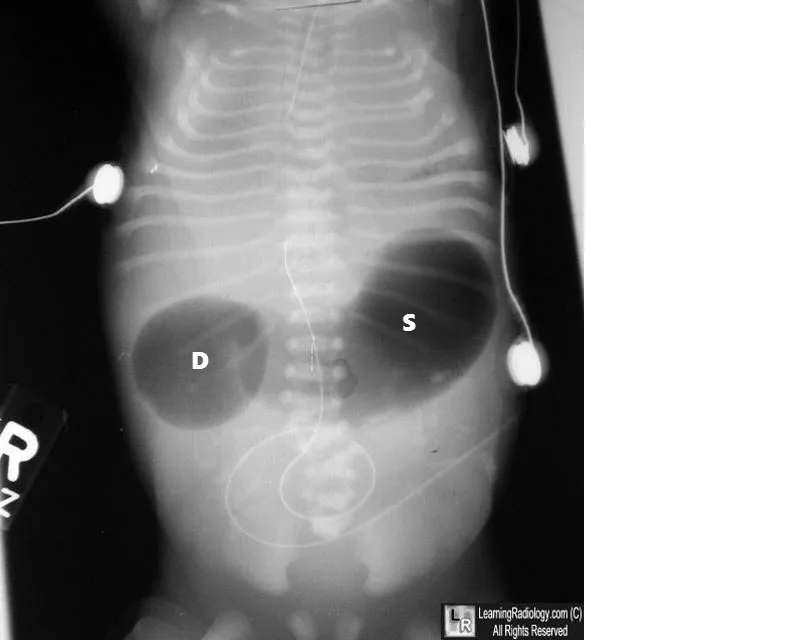

- Duodenal Atresia: ⭐

- Classic sign: "Double bubble" on X-ray.

- Associated with Down Syndrome (Trisomy 21).